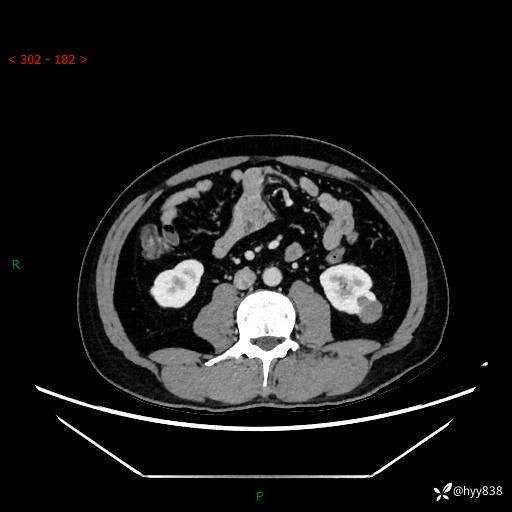

中年男性,左侧腰背部间断性胀痛不适。第一眼“乳头或囊肿”,有无意外---(有结果)

【患者信息】:41岁/男

【主诉】:左侧腰背部间断性胀痛不适1周

【现病史及既往史】:患者1周前无明显诱因出现左侧腰部疼痛,呈间断性胀痛,休息后可缓解,无放射痛,偶可见肉眼血尿,无血块,无尿频尿急尿痛,无夜尿增多,无畏寒发热、咳嗽咳痰等症状。于我院查双肾CT示:左肾占位性病变,左肾下极囊性病变,左肾轻度积水,胆囊多发结石。今为求进一步诊治来我院,门诊以“左肾占位性病变”收治入院。 起病以来,患者精神佳,饮食、睡眠良好,大便正常,小便如上诉,体力体重无明显变化。

【检查】:肾脏CT平扫+增强